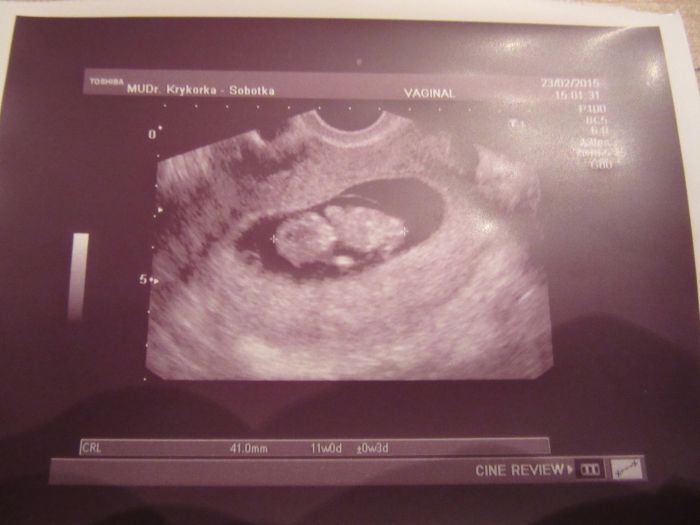

Ahoj holky, kontrola proběhla v pořádku, ale screening mi udělá až za týden, aby bylo lépe vidět projasnění a že miminko bude o trochu větší. Viděla jsem ručičky, nožičky, srdíčko jsme 11+0tt a měříme 4,1 cm . Porod máme vypočitaný na 15.9., doktor si dělal srandu, že aby nechtěl jít ven na mé narozeniny, je to nádherný pocit a jsem spokojená těhulka.